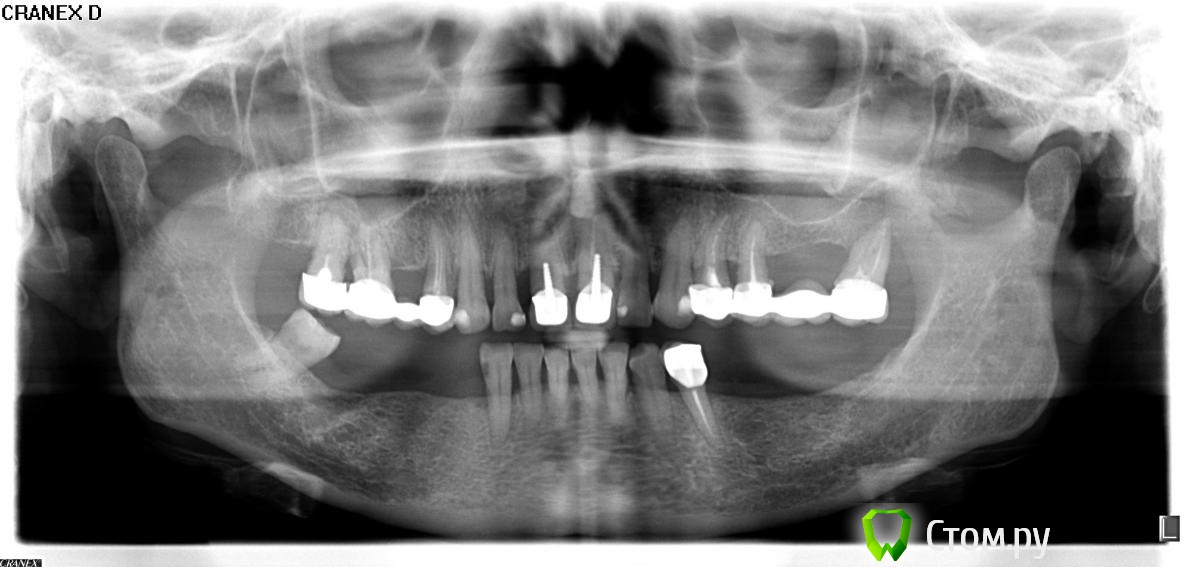

Zagoryanka Опубликовано 30 июня, 2014 Поделиться Опубликовано 30 июня, 2014 Мне 58 лет. Имплантация противопоказана по медицинским причинам.Раньше был съемный бюгель на клаймерах, стоял, как собственные зубы, аж 11 лет. Даже врачи удивлялись. Но уже год, после удаления нижней правой 6-ки, хожу без зубов в поисках варианта и врача. За это время узнала, что из-за проблем с иммунитетом основная альтернатива бюгелю отпала (имею ввиду импланты или имплататы. Так и не поняла, как правильно, но теперь и не важно).Неделю назад вскрыли флюс верхняя левая 7-ка. На снимке видна киста. Так как этот зуб мне еще несколько лет назад приговорили к удалению, теперь этого не избежать. Врач еще склоняется и к удалению нижней левой 4-ки (покачивается). Думаю и с верхними правыми 6 и7 есть проблемы, уже были флюсы с той стороныПодскажите, пожалуйста, какое протезирование возможно в моем варианте. К сожалению, доктор, ставивший мне предыдущий бюгель уже много лет живет в Чехии и потому я еще и в поиске врача. Цена не важна. Вероятно, за эти годы что-то появилось новое и в бюгельном протезировании? Снимок прикрепила. Надеюсь откроется. Спасибо Ссылка на комментарий

IvanK Опубликовано 1 июля, 2014 Поделиться Опубликовано 1 июля, 2014 Врач еще склоняется и к удалению нижней левой 4-ки по снимку - показаний не вижу проблем с иммунитетом что за проблемы? В Вашем случае, если не имплантация, то съемное протезирование. варианты лучше обсудить на очной консультации у стоматолога -ортопедаhttp://forum.stom.ru/topic/9249-posovetuite-ortopeda-v-gorode-n/page-26 Ссылка на комментарий

Mailze Опубликовано 1 июля, 2014 Поделиться Опубликовано 1 июля, 2014 Неужели такой сложный случай? Второй день надеюсь на мнение специалистов. Может вопрос поставила не правильно? При данной клинической картине (односторонний концевой дефект) и при наличии противопоказаний к протезированию с опорой на имплантаты, возможно изготовление бюгельного протеза с кламмерной фиксацией. Ссылка на комментарий

Zagoryanka Опубликовано 3 июля, 2014 Автор Поделиться Опубликовано 3 июля, 2014 Вчера была на консультации у 4-х ортопедов. Приговор единый у всех никаких бюгелей, или съемный протез или имплантация. Что делать даже не знаю. Обычный протез носить не смогу, к небу не могу дабе прикоснуться, а рисковать и имплантацией страшно. Все четыре врача сказали, что для бюгеля недостаточно опоры. Под удаление попадают нижний левый 4, верхняя левая 5-ка и 7, правая 6 и 7, а судьба остальных еще определится после снятия коронок. Что делать даже не знаю Ссылка на комментарий